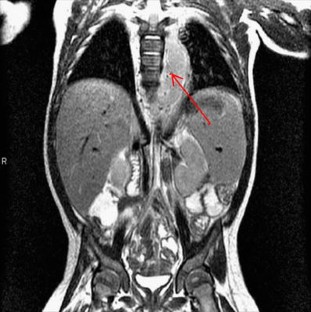

We present a case of a child born with a birthmark over the lumbar spine, which harbored a pinhole-sized opening. At 6 months of age the child presented with fever of unknown origin. Subsequent lower extremity pain resulted in imaging studies that revealed a spinal mass with extension into the posterior mediastinum. At operation, the child was found to have an infected dermal sinus tract.

This case highlights the importance of a thorough examination of the midline craniospinal axis in children with fever of unknown origin. To our knowledge, this is the first reported case of an infected dermal sinus tract with extension into the posterior mediastinum.

Fig. 2